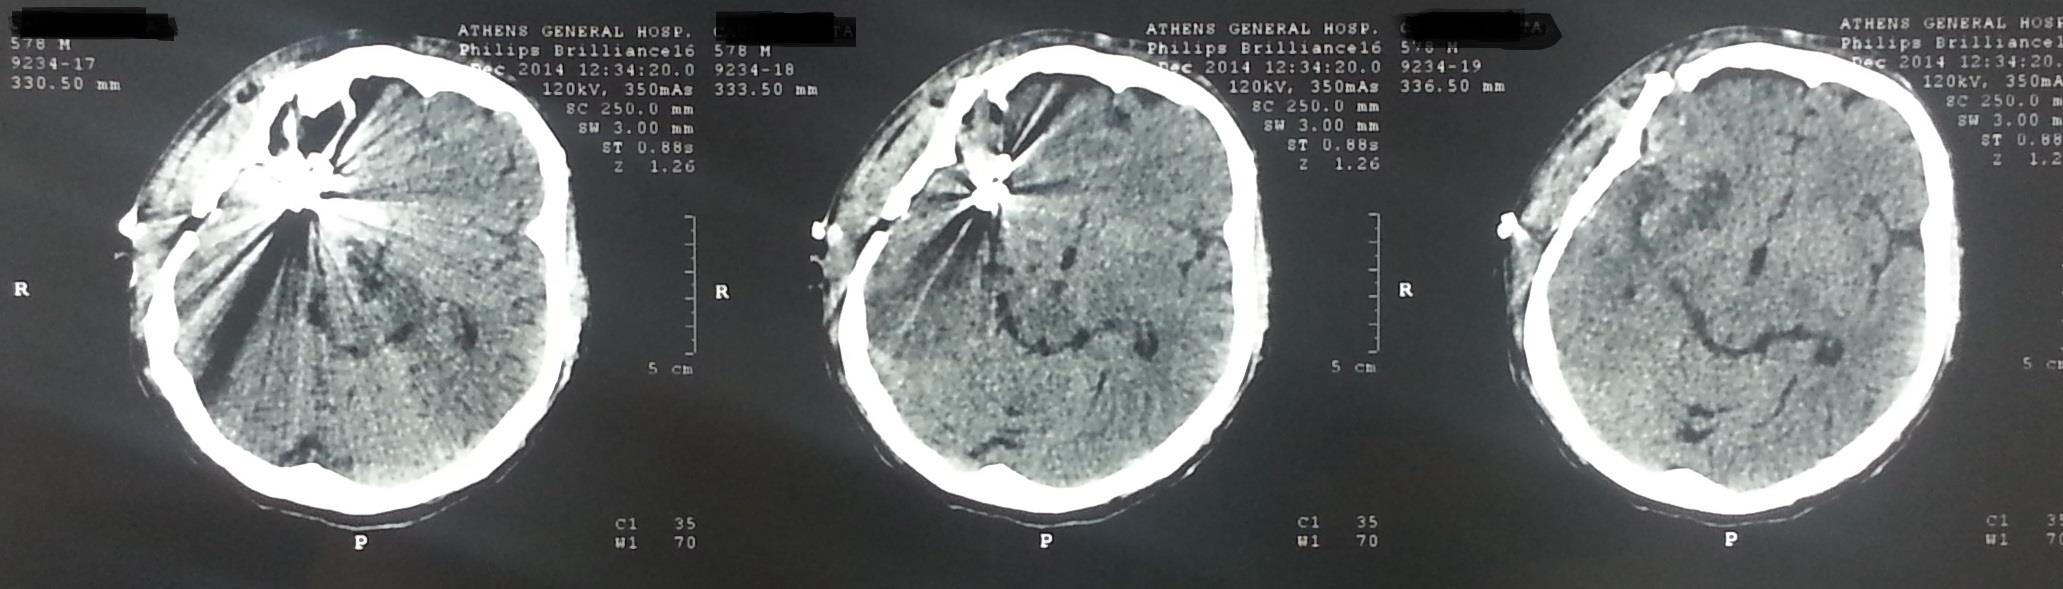

Μετεγχειρητικός απεικονιστικός έλεγχος